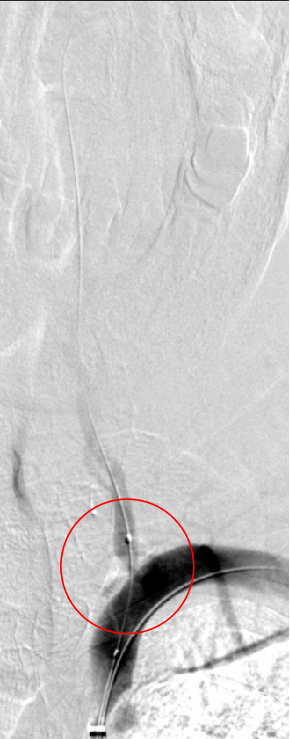

球囊预扩:

将2.0mm×20mm球囊扩张导管部分送至左侧椎动脉狭窄段,造影确认后,以8 atm行预扩张,患者无不适,回撤球囊、复查造影,提示狭窄程度部分改善。

支架定位及释放:

沿导丝将4.0mm*16mm Bridge椎动脉雷帕霉素靶向洗脱支架送到目标位置,确认定位准确后,以骨性标志为参考,缓慢加压释放支架,造影确认支架位置准确。

球囊后扩:

V1起始处管腔直径略小,予球囊后扩。造影确认管腔形态较前改善,支架贴壁良好,无支架内血栓形成、夹层或栓塞等情况,颅内血流较前明显改善,结束手术。